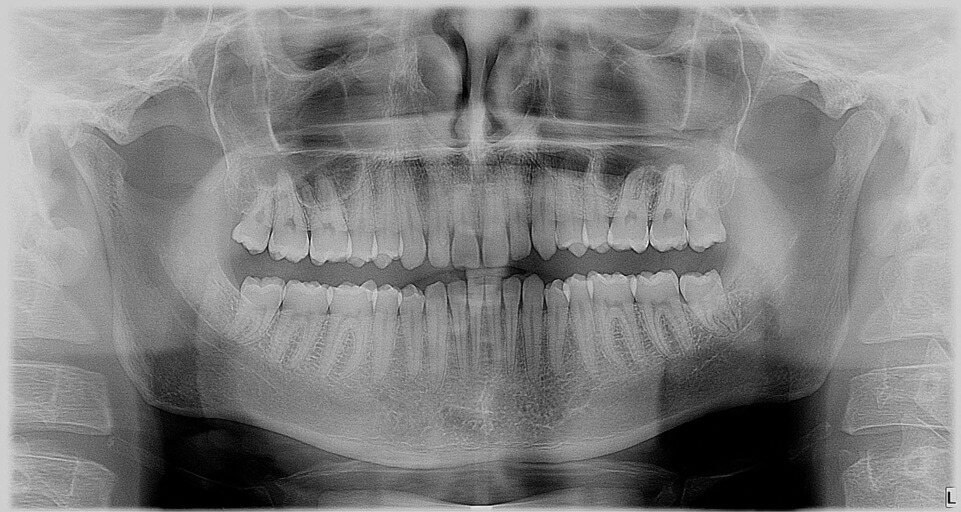

I was wondering if you could take a look aat the x-ray photo to determine whether the left side of my jaw grew bigger than the left. If this is the case, what treatment options are there to correct this problem? Ive heard of dental appliances, are there any others?

It is difficult to diagnose jay irregularities from a two dimensional radiograph. In order to diagnose and treat any abnormality, you would need to have a CT scan completed. This would allow an oral surgeon to diagnose you properly at a consultation visit along with an intra-oral and extra-oral examination. There is not any necessary treatment for jaw asymmetry unless it is causing pain or malocclusion. Most dental appliances are placed during adolescence while you are still developing and the maxilla has not completely fused. After a consultation and diagnosis with an oral surgeon, you may need to see an orthodontist, as many times the two will develop a treatment plan together for the best overall treatment goals and outcome.